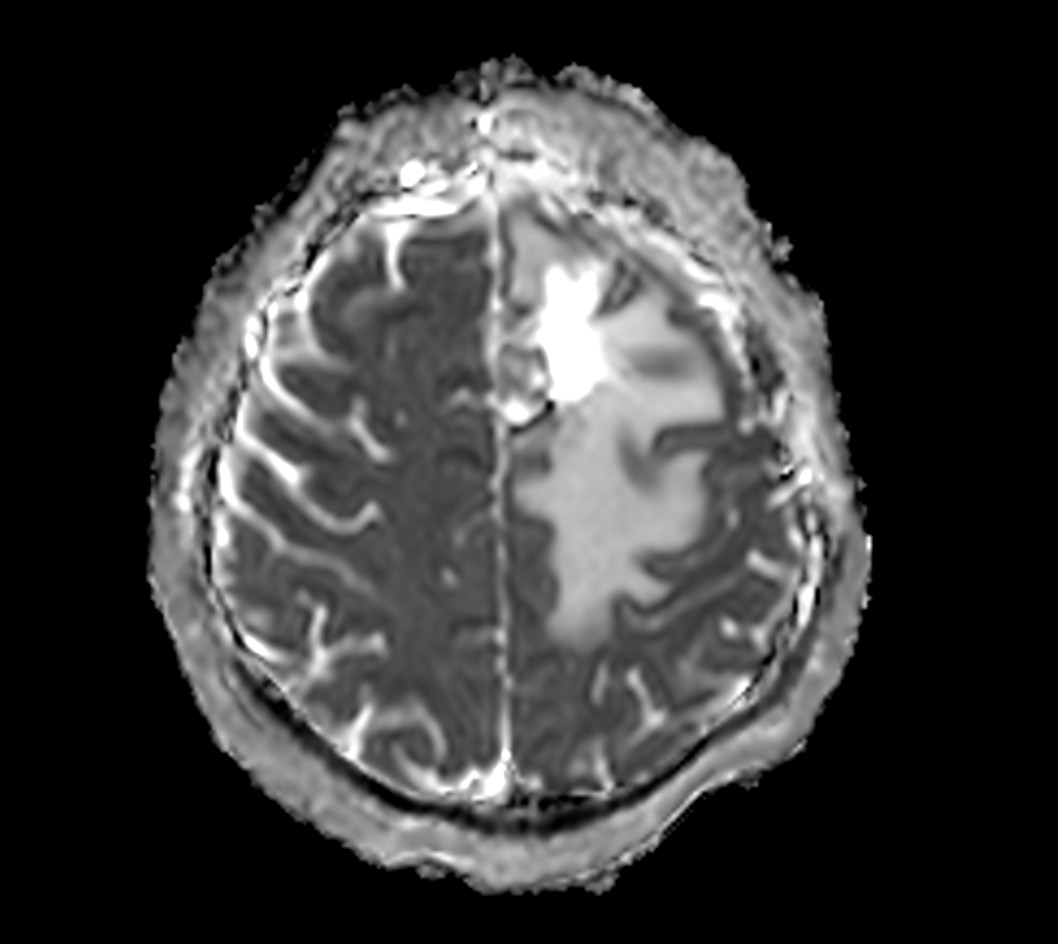

SmartSpeed Precise imaging for brain with glioblastoma

Kyushu University Hospital Japan